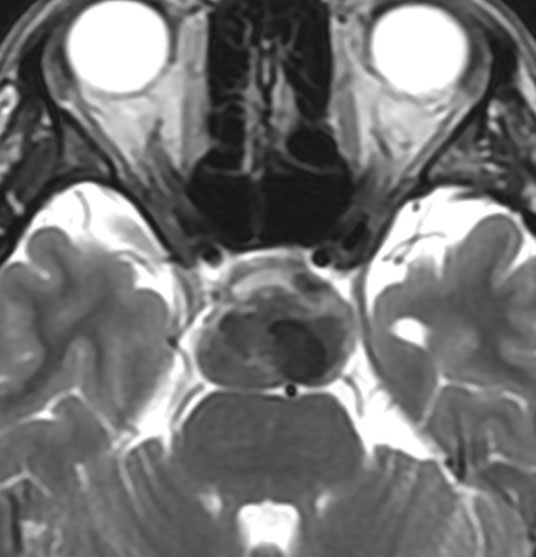

内胚葉のう胞,コロイドのう胞,ラトケのう胞ともいえる例

5歳の時に発見され23歳まで18年間経過観察をされてきた患者さんです。腫瘍はゆっくり,しかし確実に増大して,手術前には頭痛がひどく薬も効かず歩けなくなったという症状でした。術後に頭痛が無くなったので,のう胞による症状だったのでしょう。

下垂体柄の周囲にのう胞性腫瘍があります。T1強調画像では等信号,T2強調画像ではまだらな信号になっています。23年という長い経過から液状内容物が固形化したものと推定されます。T2で低信号となる部分があるのですが,黄色肉芽腫とは異なる像です。

下垂体柄は長く伸びています。のう胞による長期の圧迫のため斜台上部がerosionになって凹んでいます。トルコ鞍内の中間葉の位置に典型的な小さなラトケのう胞(黄色矢印)がみられますが,これは長年変化していませんでした。

左前頭側頭開頭 pterional approachで,のう胞壁を含めて完全摘出 complete removalしました。のう胞は下垂体柄の左側に付着してそこから発生したものでした。内容物は固体で寒天状のコロイドでした,一部軟らかくて一部は線維化していました。のう胞壁は半透明で薄い部分も線維性の膜状の部分もありました。病理検査では上皮細胞が証明されて内胚葉のう胞 endodermal cystの診断です。

ラトケのう胞はhiatusから内容液吸引だけして,皮膜はもちろんそのままにしています。